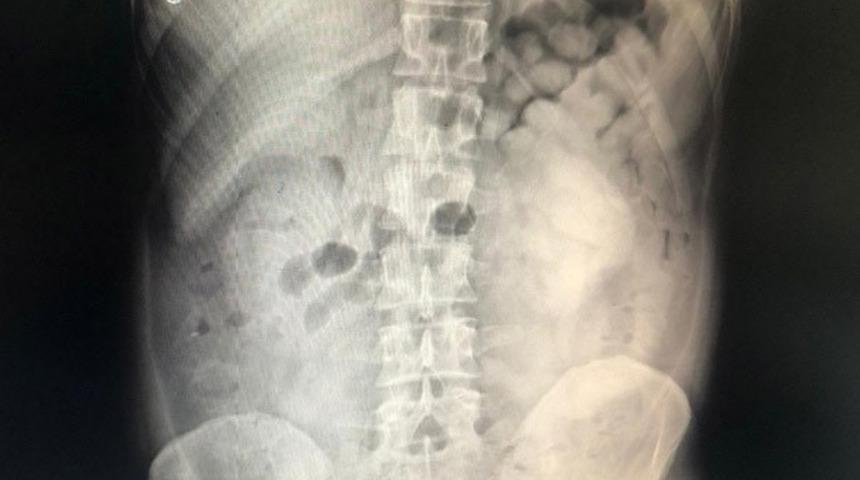

Doktor muayenesi ve çekilen film sonucunda şüphelinin sindirim sisteminde 800 gram eroin maddesi ele tespit edildi.